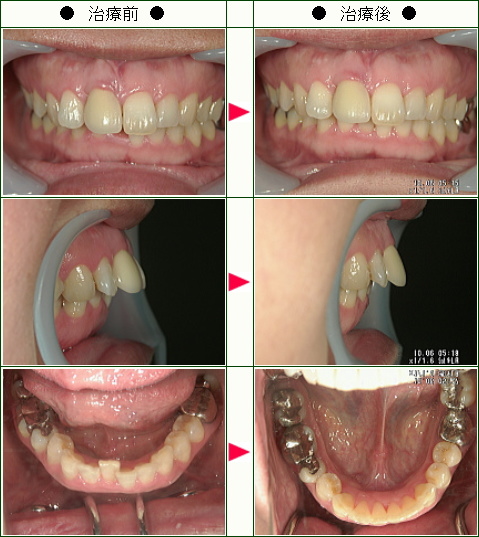

☆デコボコ症例(K様 40歳 女性)

▼患者様の感想

欠けた歯を治すのに、「矯正をした方が良い」とかかりつけの歯科医に勧められたのがきっかけで、矯正歯科を探しました。

部分矯正をされていて評判が良かったので、こちらにお願いをしようと決めました。

治療期間はワイヤーが約3ヶ月、マウスピースが約半年でした。

先生は私の歯並びでは全体矯正の方が良いとおっしゃられたのですが、治療費、期間の事で、部分矯正をお願いしたところ、快く治療して下さり有難く思いました。

治療中は歯の痛み、口内炎が辛かったです。

どのスタッフの方も対応は素晴らしく、嫌な思いをしたことは一度もありませんでした。

待ち時間は、時々すごく待たされることがあり、それは残念だったと思いました。